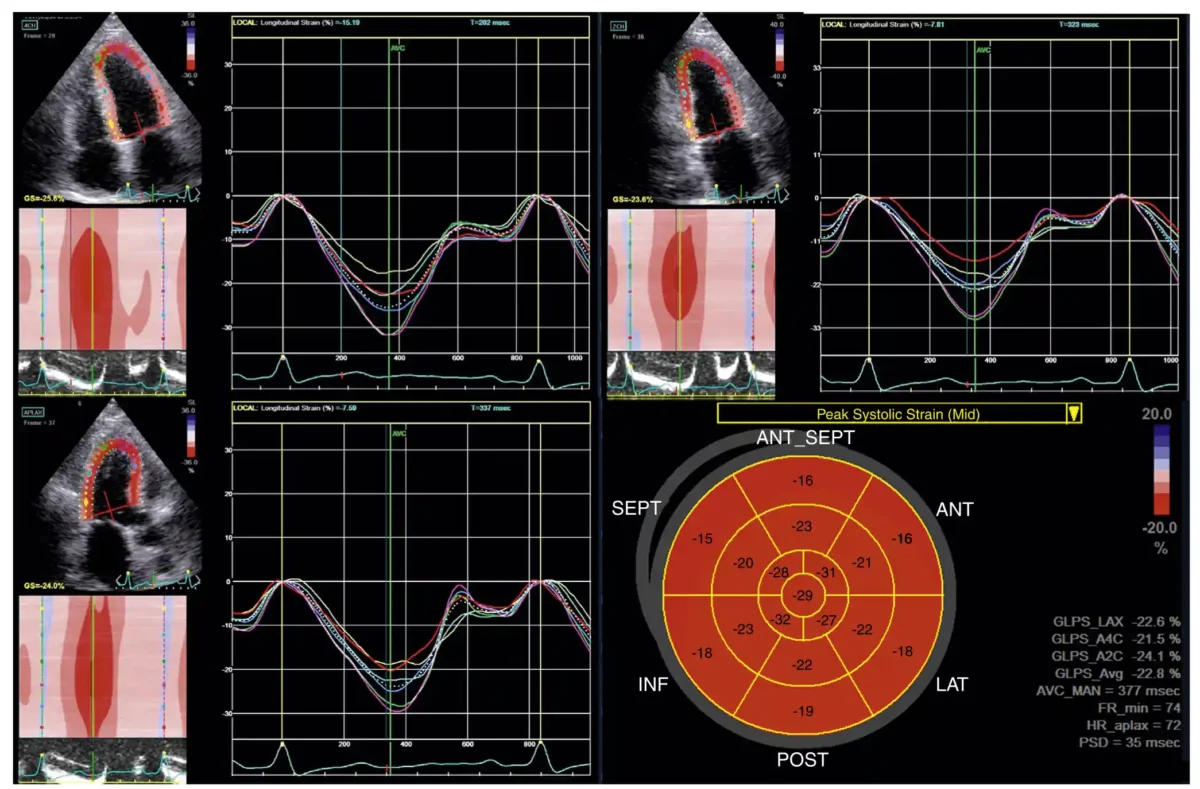

نمونه‌ای از استرین طولی که برای تعیین استرین طولی سراسری (GLS) استفاده می‌شود. نمای اپیکال چهارحفره (بالا چپ)، نمای اپیکال دوحفره (بالا راست)، نمای اپیکال لانگ‌اکسیس (پایین چپ)، و نمودار قطبی بولزآی (پایین راست). مقدار GLS در این مثال برابر با ۲۲.۸٪ است (بر حسب مقدار مطلق).